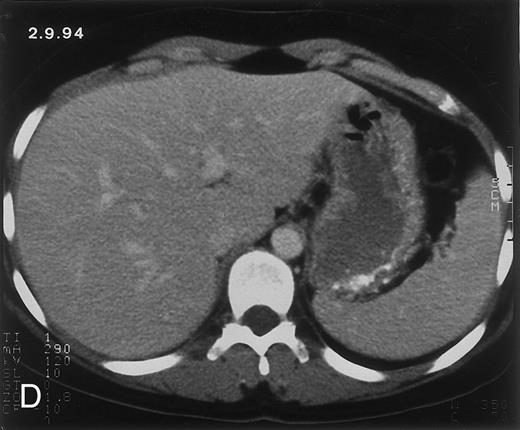

Radiologic evolution in patient B. (A) Postcontrast abdominal CT scan on February 10, 1994 shows multiple small hypodense areas in all segments of the liver suggestive of hepatic candidiasis. Twenty-four days previously, the patient had recovered from severe neutropenia after the second cycle of chemotherapy for ALL. (B) On May 4, 16 days after the neutrophil count had dropped below 500/μL in the third chemotherapy cycle, there is clear improvement of the radiologic findings, with only a few hypodense areas in the liver.

(C) On June 6, 31 days after normalization of neutrophils, CT again shows multiple lesions in the liver (arrowheads) with a different presentation: the small lesions show strong peripheral enhancement. (D) On September 2, 129 days after neutrophil recovery, all hepatic lesions have completely resolved.

Evolution of fungal lesions on CT scans during and after neutropenia is summarized in Table 2. Figure 1 (patient A) and Fig 2 (patient B) serve to illustrate Table 2.

In three patients, multiple round lesions were seen on postcontrast CT scans of the abdomen in the liver and the spleen, while in two cases, lesions could only be seen in the liver (Table 2). Following the diagnosis of disseminated candidiasis, these lesions decreased in size and visibility during subsequent neutropenia in three patients (compare Fig 2A and B) and disappeared completely in two patients (compare Fig 1A and B). The numbers of days of severe neutropenia (neutrophils <500/μL) at the time the CT scan was performed are listed in Table 2. After recovery from neutropenia and despite continued antifungal therapy, the size and visibility of the lesions increased again (Fig 1C). Similarly, the number of days since recovery from severe neutropenia (neutrophils >500/μL) are listed in Table 2. In two of three patients treated with another cycle of myeloablative chemotherapy, this waxing and waning pattern of radiologic lesions could be seen again (Fig 1D and E). In all patients, lesions eventually disappeared (Figs 1F and 2D) after prolonged antifungal therapy.